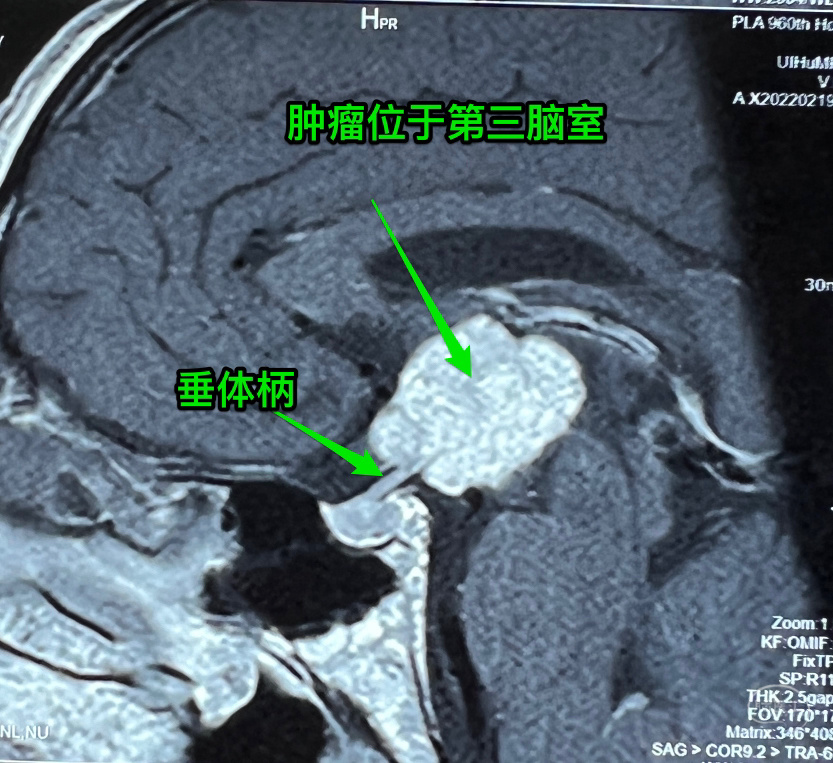

病例简介:中年男性,视力下降,无内分泌及下丘脑损害表现。术前生殖细胞肿瘤相关检查阴性,术中病理:造釉细胞型颅咽管瘤,常规病理尚未报出。

根据术前影像,属于漆松涛教授QST分型中的S或T型,实际上起源点在影像上不容易准确判断,所以较难判断到底是S型还是T型。

根据洪涛教授分型,属于中央型,但肿瘤偏向左侧。

根据国外学者分型,属于视交叉后型,肿瘤偏后,术中也证实了在视交叉后。目前没有哪一种分型能解决所有的病例问题。

术前